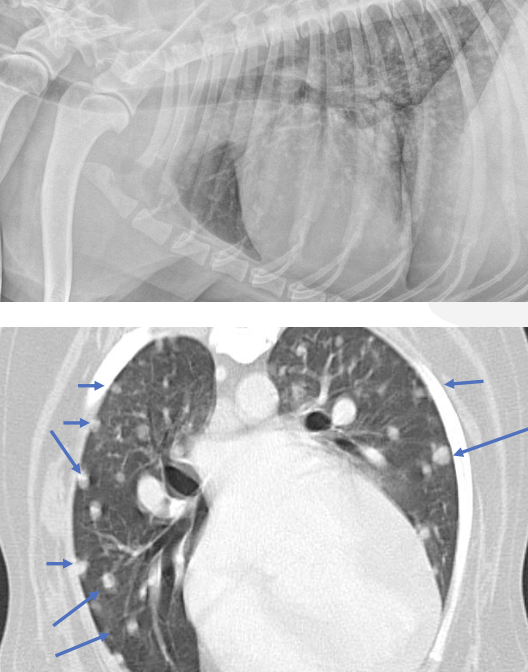

-thoracic imaging (radiographs or CT)

-abdominal imaging (radiographs, ultrasound, or CT)

what is the purpose of thoracic imaging when diagnosing hemangiosarcoma?

search for mets:

-described as nodular to interstitial coalescing miliary pattern (ill-defined, fuzzy appearance)

radiographs: 78% sensitivity for detecting mets (false negative rate decreases w/ 3 views)